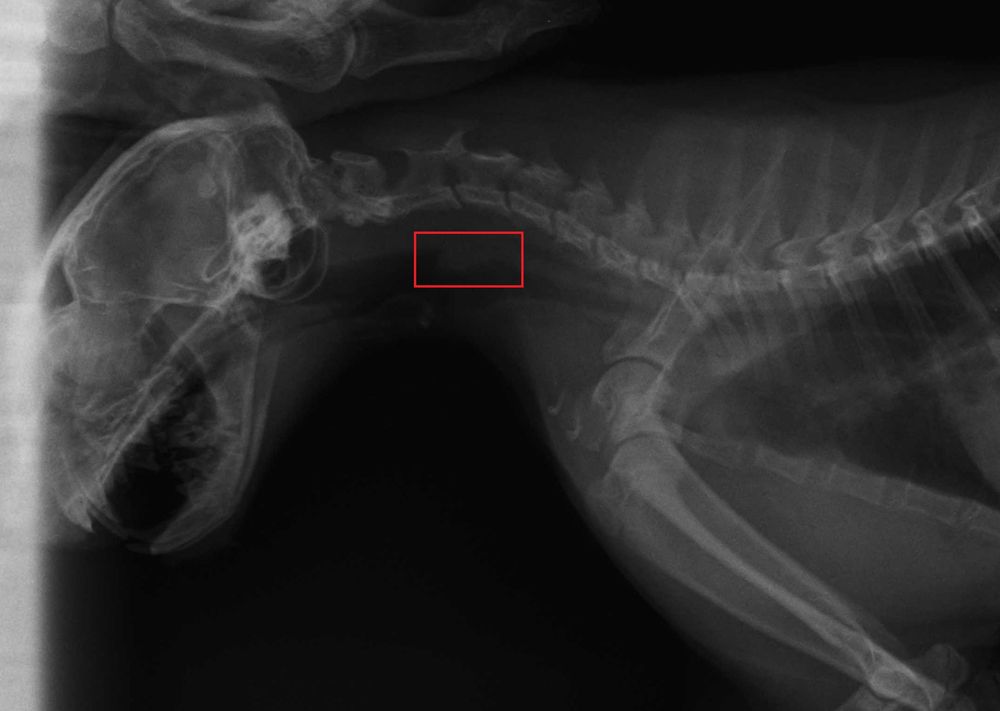

Наталья Key писал(а) 06 апр 2017, 17:40:Я за Алексея напишу. Он сейчас с Малышом идет на Узи к Иноземцевой. До этого делали рентген. Кот вел себя по-мужски. Дрался и сражался за независимость. Рентген вроде бы показал непонятный нарост на пищеводе. Самое плохое, что кот четыре дня не ест, не пьет. В туалет по-маленькому ходил несколько раз, в переноске выдавил несколько какашек и описался. Обезвоживание в начальной стадии.

Anna_D писал(а) 07 апр 2017, 20:09: но я убеждена, что эта загогулина - это что-то, что Малыш проглотил и что смогло там застрять

Страсти какие !!!! Не дай бог !!!!Anna_D писал(а) 07 апр 2017, 20:09:я убеждена, что эта загогулина - это что-то, что Малыш проглотил и что смогло там застрять, предварительно проткнув стенку пищевода.

Не видно никакого инородного тела ни на рентгене ни на УЗИ .....Мунтик писал(а) 07 апр 2017, 20:32:Я тоже "за" инородное тело

E-Alex писал(а) 07 апр 2017, 20:37:Не видно никакого инородного тела ни на рентгене ни на УЗИ .....Мунтик писал(а) 07 апр 2017, 20:32:Я тоже "за" инородное тело